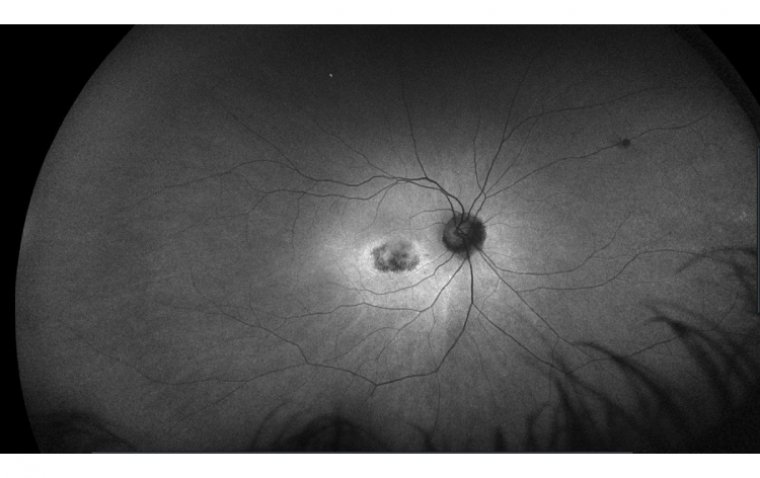

The accumulation of Plaquenil in the RPE cells and the photoreceptor cells can lead to cellular damage and death, which can cause visual symptoms. The damage can also result in the formation of deposits in the retina known as "bull's eye maculopathy" or "flying saucer sign." These deposits can be seen on an eye exam and are a hallmark sign of Plaquenil retinal toxicity.